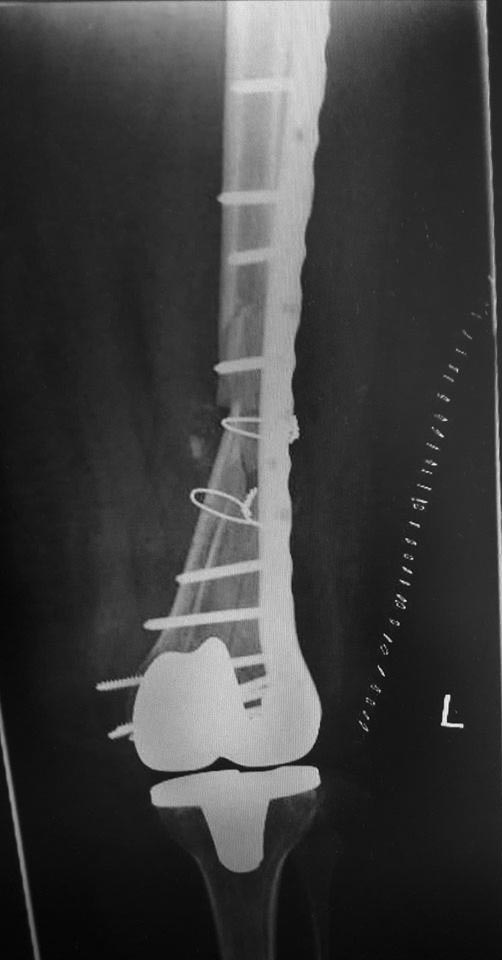

эКак оказалось в нашей ЦРБ сделали уже сегодня шеф решил без СТ. Пациент 41 года с большим количеством патологии. То есть полных 76 лет.

Принципиальный момент- стабилен ли бедренный компонент? Если компонент изначально стабилен, что в данном случае мало вероятно), то все ок. Наилучшие результаты при использовании ИМ остеосинтеза (хотя могут быть проблемы с репозицией и размером гвоздя), затем блокированные пластины, затем все остальное ( последнее время много статей про применение аппаратов наружной фиксации). В данном случае длинна пластины корректная, но в зоне перелома слишком много металла, выше перелома должно быть 4-5 винтов, все бикортикально, с чередованием с пустыми отверстиями. То, что внизу торчат винты не очень good, но не так страшно. Консервативное лечение сопряжено с высоким риском летальности в течение первого года после травмы, вполне сравнимым с не оперированными шейками. Ключевой вопрос - стабильность бедренного компонента, теперь риторический).

А что правда кто-либо считает этот остеосинтез хорошим? По-моему беда! Шансов на сращение крайне мало, а для пожилого человека это может быть конец. Все принципы нарушены...

76 лет, остеопороз. В таких условиях требуется максимальное сохранение кровоснабжения в зоне перелома и фиксация с соблюдением принципа шинирования. Оно может быть накостным, интрамедуллярным или при помощи АНФ. В данном случае операция открытая, очень травматичная, куча винтов в зоне перелома, которые там неизвестно зачем, ну и серкляжи, которые могут стать последней каплей в убийстве кости. Из хорошего это действительно длина пластины, но при таком расположении винтов она (длина) не работает

Скорее всего, бедренный компонент не отклеился, так что это Rorabeck-Lewis II. Традиционный вариант - пластина с угловой стабильностью закрыто. Или две, чтобы от варусного коллапса подстраховаться. Мне больше бы импонировал антеградный закрытый интрамедуллярный остеосинтез.

Добрый вечер, джентельмены!

1. Чаще всего у пациентов этого возраста перипротезный перелом после ЭПКС - последствие низкоэнергетический травмы на фоне выраженного остеопороза. Т.е. согласен с Михаил Панин, что следует поберечь кровоснабжение.

2. При определении тактики лечения таких пациентов, если оперативное лечение конечно возможно, ключевыми являются два фактора: стабильность бедренного компонента и размер дистального фрагмента. Если бедренный компонент нестабилен об остеосинтезе речи быть не может.

4. Принципы мостовидного остеосинтеза на показанных картинках не реализованы, в этом Панин безусловно прав.

Количество эндопротезирований растёт, поэтому с подобными случаями придётся сталкиваться чуть не каждому из нас. Или каждому. Думаю, следование принципам - абсолютная стабильность вокруг компонентов протеза и относительная - вне, не может вызывать особых дискуссий.

К сожалению (при этом желаю и хирургу, и пациенту удачи), выполненное вмешательство оставляет крайне мало шансов больному. Именно потому, что для метадиафизарной части перелома доктор пытался добиться абсолютной стабильности. Что не приемлемо при остеопорозе. Там и случится проблема, возможно, в самое ближайшее время. Я бы использовал остеосинтез пластиной - миниинвазивный для метадиафизарной зоны (как я понимаю, мы предполагаем, что ножка стабильна? ОК). Вот эти винты и завитушки на диафизе лишние и только демонстрируют не вполне гуманное отношение к биологии в этой зоне.

Учитывая, что протез без стабилизатора, межмыщелковое пространство абсолютно свободно и оптимальным вариантом в данном случае мог стать ретроградный интрамедуллярный остеосинтез с блокированием как самый малоинвазивный и сохраняющий и без того того повреждённое кровоснабжение через надкостницу. Выполненный накостный остеосинтез нельзя отнести к стабильному, к тому же по представленным рентгенограммам складывается впечатление, что винты проведённые через мыщелки обычные кортикальные, не фиксированы в пластине, серкляжные швы не придают стабильности. Потребуется длительная контролируемая реабилитация. Не исключается по результатам рентгенконтроля повторное оперативное вмешательство (костная пластика или всё-таки переход на интрамедулляный остеосинтез)